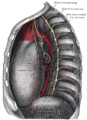

يغطي الحجاب الحاجز من الجهة العليا الملامسة للرئتين البطانة التي تبطن الصدر وهي ال Parietal Pleura ، و يكون الرباط المركزي ملاصقا لغلاف القلب The Fibrous Pericardium . اما من الجهة السفلى للحجاب الحاجز فانه يغطى بالغلاف المبطن للاحشاء في البطن و هو ال Perietal Peritoneum ما عدا في منطقة واحدة فانه يلامس سطح الكبد مباشرة وهذه المنطقة هي ال Bare Area و تقع في الفص الايمن من الكبد .

للوريد الكبير السفلي ( بمستوى الفقرة T8 ): يمر الوريد السفلي عبر فتحة في الرابط المركزي اي ليس عبر الياف العضلات و الحمد لله لانه لو كان يمر عبر العضلات لتقلصلت عليه و سدت مجرى الدم فيه لان جداره رقيق .

للمرئ ( بمستوى الفقرة 10 T ): فتحة المرئ تقع قليلا إلى اليسار لكن تحيط بها الياف عضلية من القسم الايمن للحجاب الحاجز . يمر عبر هذه الفتحة ايضا شرايين تاتي من الشريان المعدي الاسفل وهي تتصل بشريان اخرى و تعتبر احدى الاماكن التي تتصل بها الدورة البوابية ( التي تذهب إلى الكبد ) مع بقية الدورة الدموية في الجسم PORTO-SYSTEMIC SHUNT ومن هذه الفتحة يمر العصبين المسمايين : العصبين التائهين الامامي والخلفي ANTERIOR AND POSTERIOR VAGUS NERVES

للابهر ( بمستوى الفقرة T 12 ): بالنسبة للفتحة الثالثة فهي في الخلف ويمر عبرها الشريان الابهر من الصدر إلى البطن ، وتقع هذه الفتحة في الوسط ويمر عبرها ايضا القناة التي تحمل السائل اللمفي المسماة : THORACIC DUCT .